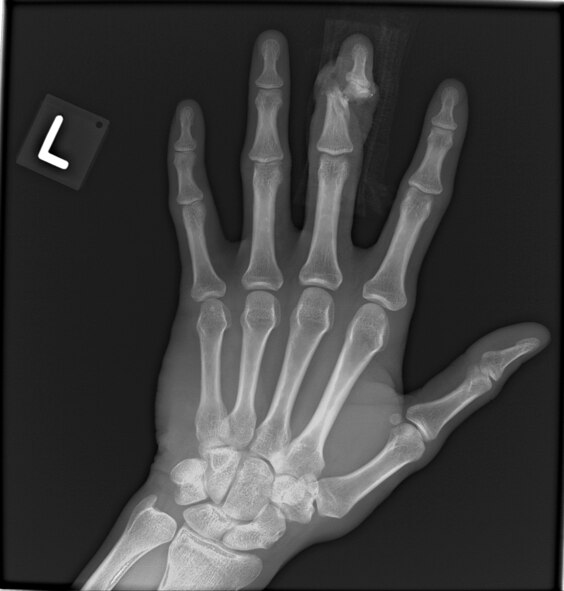

An X-ray of Airman 1st Class Daniel Cherry's left hand depicts where his middle finger was nearly sliced in two by a 4,000 pound pallet. Cherry, a C-17 Globemaster III loadmaster deployed from Charleston Air Force Base, S.C., was loading cargo onto an aircraft when his finger became stuck on a D-ring and was nearly amputated between a pallet and loading rail. (courtesy photo)